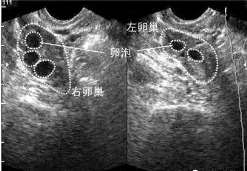

查看全文做试管的全部过程是什么? 试管婴儿全过程是什么试管婴儿的过程包括:从卵巢内采集成熟卵母细胞(取卵),从男性伴侣 […]